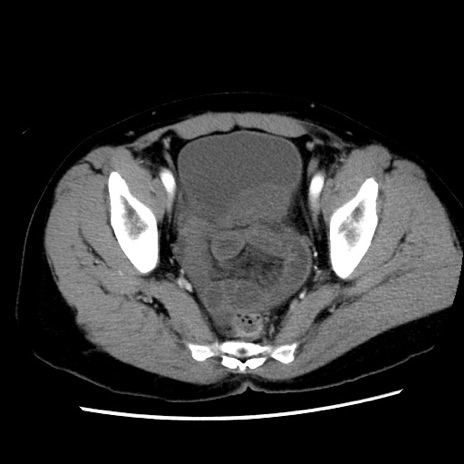

症例10(横断像)

【症例】 50歳代女性

【主訴】 腹痛

【現病歴】前日生レバーを食べた。今朝に排便あり。 昼前に突然発症の腹痛を生じ、当院救急外来を受診した。

【既往歴】 子宮筋腫にてで子宮全摘後

【身体所見】 意識清明、腹部:平坦、軟、下腹部やや左を中心に圧痛・反跳痛あり、筋性防御あり

【データ】WBC 7800、CRP 0.07